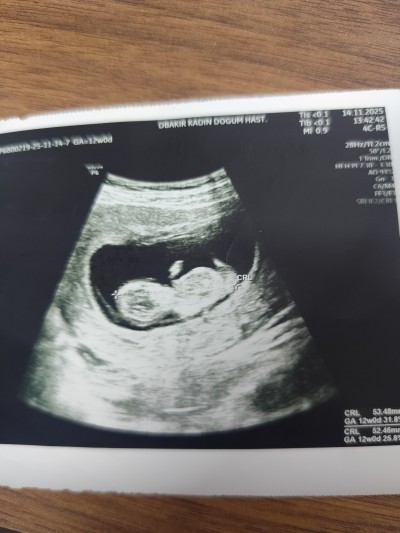

Cinsiyet tahmini yapalım bir defa paylaştım kimse yorum yapmadı sadece 2 kişi

Kapatılma nedeni: İsim tavsiye veya cinsiyet tahmini gibi soruların sohbet alanında sorulması gerekmektedir. Menüden gebelik dışı konular için ayrılmış alanda konunuzu açabilirsiniz..